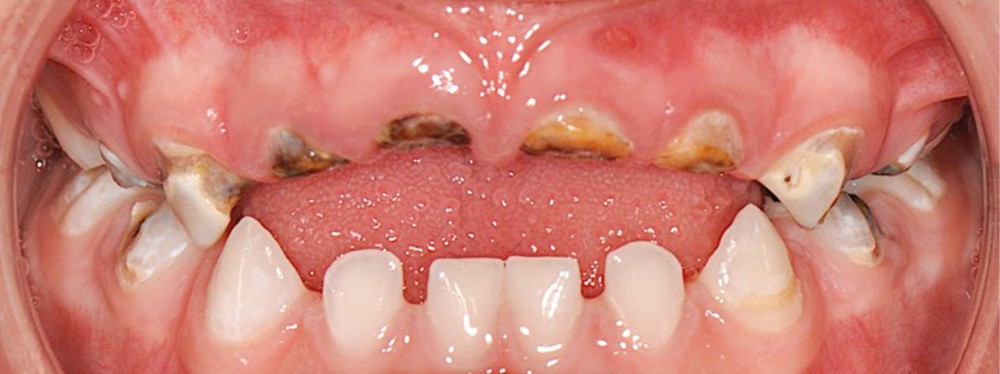

L’OMS recommande un allaitement exclusif jusqu’à l’âge de 6 mois, et associé à d’autres aliments jusqu’à 24 mois [3]. S’il n’est plus nécessaire de démontrer les bienfaits de l’allaitement sur la santé globale de l’enfant, il reste néanmoins utile d’en prévenir certaines pratiques parfois inadaptées pouvant conduire à l’apparition de carie de la petite enfance (CPE) (fig. 1 et 2). L’allaitement au sein exclusif pendant une période de 6 mois présente bien des avantages pour le nourrisson et la mère, et notamment celui de protéger contre les infections gastro-intestinales, aussi bien dans les pays en développement que dans les pays industrialisés. Par ailleurs, une mise au sein précoce, dans l’heure qui suit la naissance, réduit le taux de mortalité.

Les études soulignent également les bienfaits de l’allaitement sur la santé orale : il favorise notamment le développement de la musculature, la croissance maxillo-faciale et limite les malocclusions chez l’enfant [4]. Si la cariogénicité du lait maternel n’a pas été examinée de manière approfondie, des études suggèrent qu’elle est plus importante que celle du lait de vache, mais moins importante que celle des préparations infantiles. Ceci est à considérer notamment lors de consommations fréquentes [5, 6]. Par conséquent, il a été mis en évidence que l’allaitement maternel pourrait être un facteur de protection contre la CPE jusqu’à l’âge de 12 mois. Pour autant, des pratiques d’allaitement à la demande, après l’éruption des dents temporaires, et notamment la nuit, associées à des pratiques de cosleeping (ou co-dodo : l’enfant dort avec la mère), contribueraient à développer la CPE après 12 mois [7, 8]. Si d’autres facteurs sont également à considérer dans le développement de la CPE [9], les études soulignent que l’allaitement prolongé [au-delà de 24 mois]…